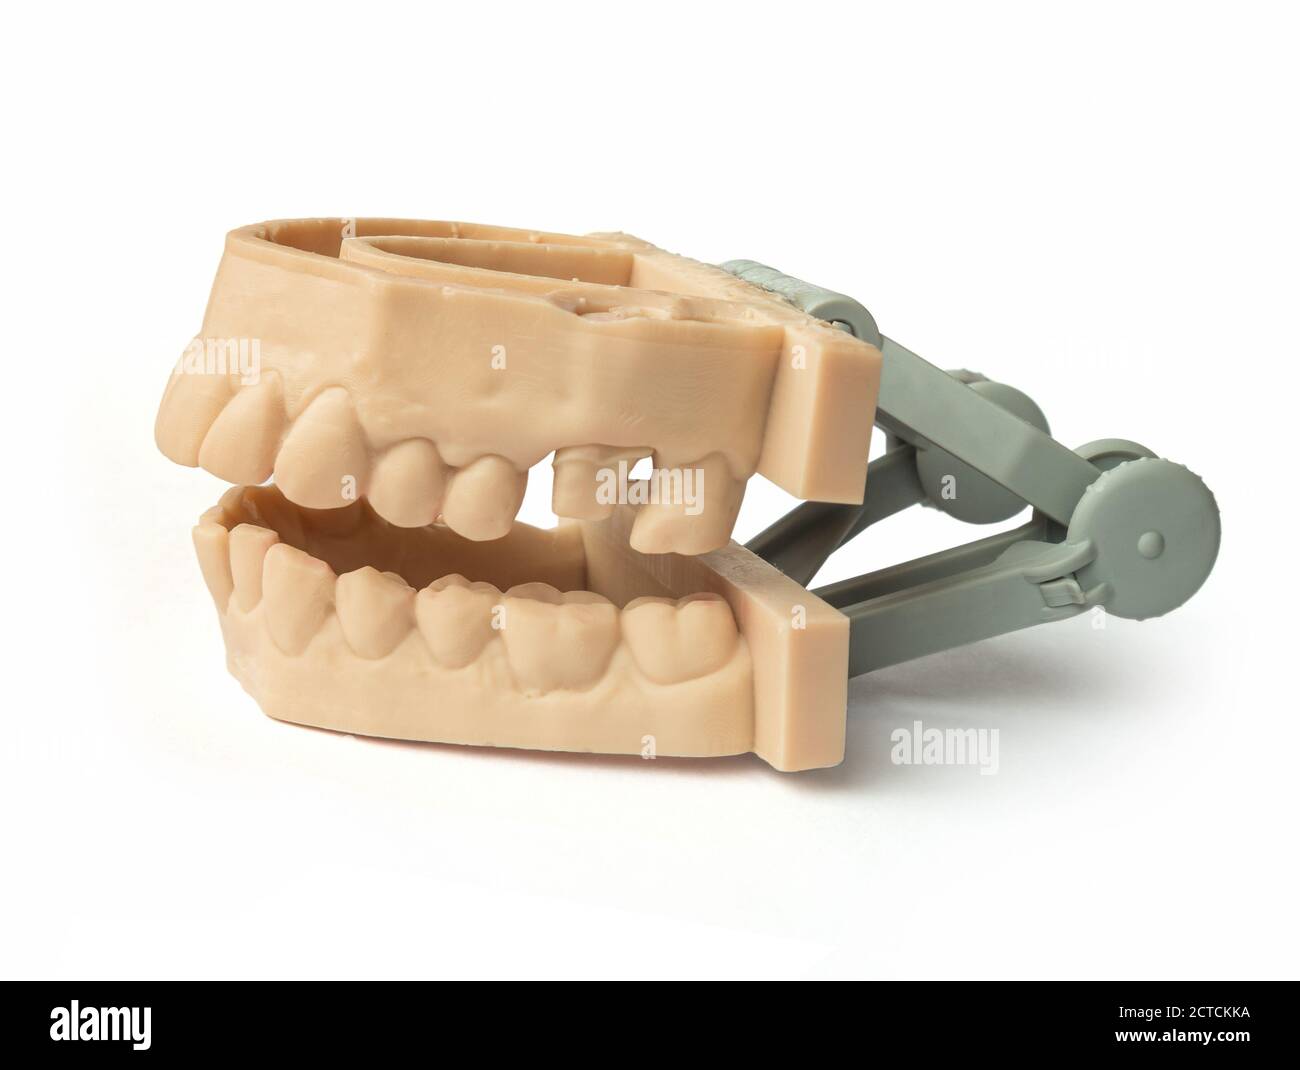

Dents imprimées par une imprimante 3d. Mâchoire supérieure et inférieure pour adulte. Utilisé pour créer des aligneurs, des gardes de nuit, des bretelles, des couronnes, des prothèses dentaires et des guides chirurgicaux, Isola Banque D'Imageshttps://www.alamyimages.fr/image-license-details/?v=1https://www.alamyimages.fr/dents-imprimees-par-une-imprimante-3d-machoire-superieure-et-inferieure-pour-adulte-utilise-pour-creer-des-aligneurs-des-gardes-de-nuit-des-bretelles-des-couronnes-des-protheses-dentaires-et-des-guides-chirurgicaux-isola-image376448334.html

Dents imprimées par une imprimante 3d. Mâchoire supérieure et inférieure pour adulte. Utilisé pour créer des aligneurs, des gardes de nuit, des bretelles, des couronnes, des prothèses dentaires et des guides chirurgicaux, Isola Banque D'Imageshttps://www.alamyimages.fr/image-license-details/?v=1https://www.alamyimages.fr/dents-imprimees-par-une-imprimante-3d-machoire-superieure-et-inferieure-pour-adulte-utilise-pour-creer-des-aligneurs-des-gardes-de-nuit-des-bretelles-des-couronnes-des-protheses-dentaires-et-des-guides-chirurgicaux-isola-image376448334.htmlRF2CTCKKA–Dents imprimées par une imprimante 3d. Mâchoire supérieure et inférieure pour adulte. Utilisé pour créer des aligneurs, des gardes de nuit, des bretelles, des couronnes, des prothèses dentaires et des guides chirurgicaux, Isola

- Ouvrir la bouche dents adultes modèle avec des mâchoires supérieure et inférieure et de ses trente-six dents permanentes. Banque D'Imageshttps://www.alamyimages.fr/image-license-details/?v=1https://www.alamyimages.fr/photo-image-ouvrir-la-bouche-dents-adultes-modele-avec-des-machoires-superieure-et-inferieure-et-de-ses-trente-six-dents-permanentes-84712216.html

- Ouvrir la bouche dents adultes modèle avec des mâchoires supérieure et inférieure et de ses trente-six dents permanentes. Banque D'Imageshttps://www.alamyimages.fr/image-license-details/?v=1https://www.alamyimages.fr/photo-image-ouvrir-la-bouche-dents-adultes-modele-avec-des-machoires-superieure-et-inferieure-et-de-ses-trente-six-dents-permanentes-84712216.htmlRFEWPY88–- Ouvrir la bouche dents adultes modèle avec des mâchoires supérieure et inférieure et de ses trente-six dents permanentes.